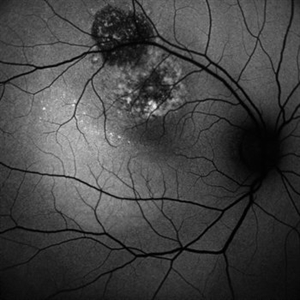

PROLIFERATIVE DIABETIC RETINOPATHY

LATE PHASE FLUORESCEIN ANGIOGRAPHY OF A 50 YEAR OLD MALE WITH PROLIFERATIVE DIABETIC RETINOPATHY

Photographer: Dr. Akansha Sharma-Retina Foundation, Ahmedabad

Condition/keywords: florid type PDR, proliferative diabetic retinopathy (PDR)